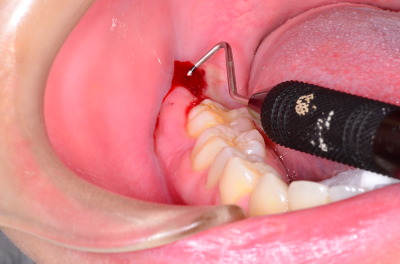

기구를 이용해서 진찰도 하면서 피고름도 배출시키고 있는 사진입니다.  기구의 검정색 줄이 10mm 정도이니까 잇몸이 6~7mm 정도 부풀어 올랐다고 할 수 있습니다.